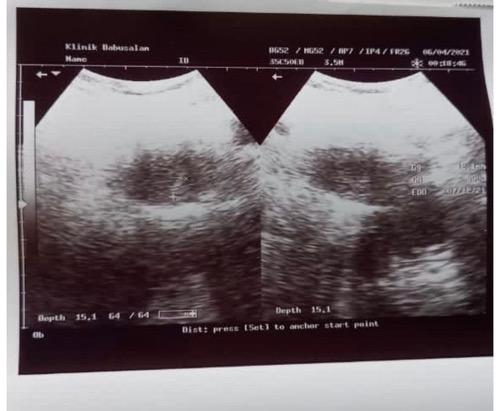

Hasil USG Jessica Iskandar. (Foto: IG)

Pada gambar tersebut, tertera foto USG itu diambil pada 6 April 2021. Artinya sudah dilakukan 6 bulan yang lalu. Selain itu, lokasi tempat pengambilan foto USG juga dipertanyakan netizen. Di foto tersebut tertera USG dilakukan di Klinik Babussalam, nama yang bisa jadi tidak pernah dikunjungi oleh Jedar.